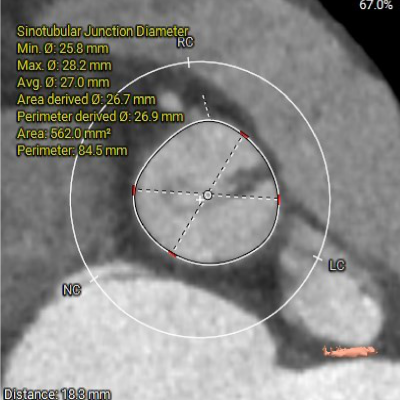

主动脉根部测量

瓣上结构测量

术前CT评估

1. Type 1 型二叶式主动脉瓣,瓣叶增厚伴中度钙化,L-N间钙化融合嵴,左室流出道呈敞口型;

2. 冠脉开口高度尚可,左右冠瓣叶冗长,切线位左右冠瓣叶长度>>冠脉开口到瓣叶根部附着缘距离;冠脉未见明显钙化斑块;

3. 三窦大小不一,瓦氏窦、窦管交界内径偏小,升主动脉轻度扩张;左室腔内径尚可,心室壁未见明显增厚;

4. 瓣环水平夹角51°,主动脉弓夹角偏锐利,弓距偏小;